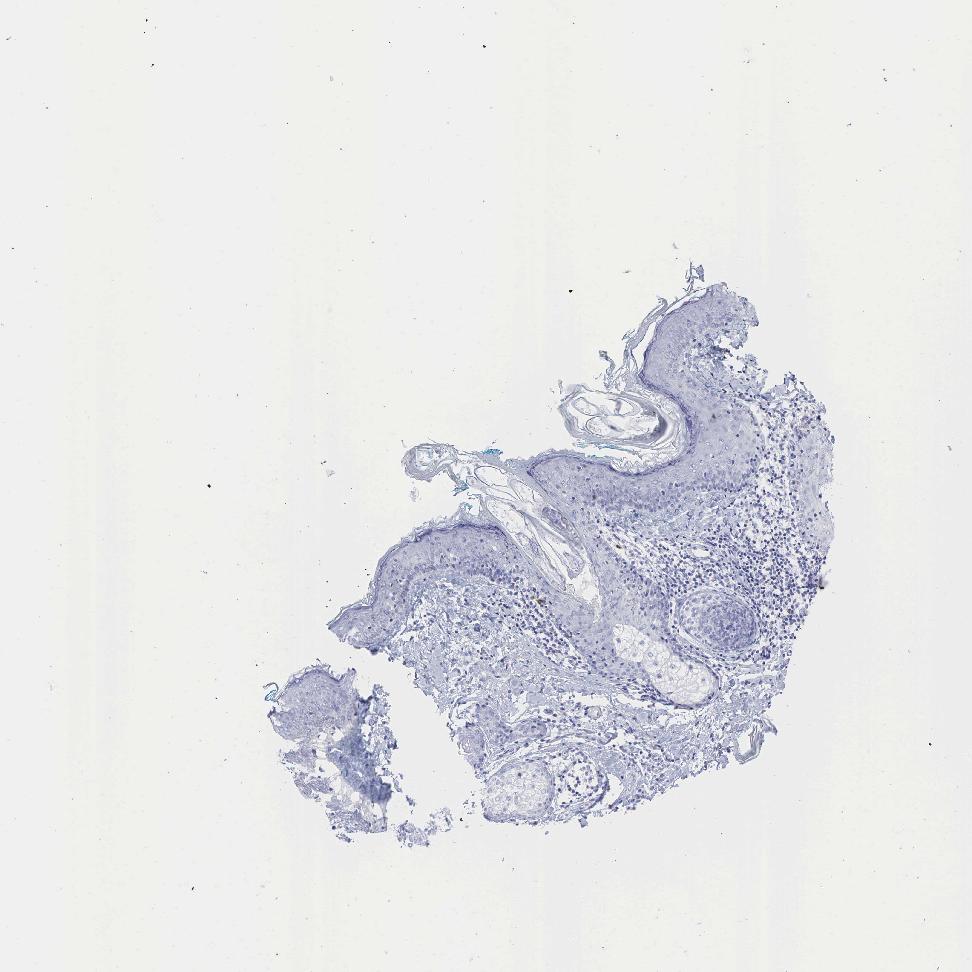

SKIN 1 - Antibody stainingi

Antibody staining in the annotated cell types in the current human tissue is reported as not detected, low, medium, or high, based on conventional immunohistochemistry profiling in selected tissues. This score is based on the combination of the staining intensity and fraction of stained cells.

Each image is clickable and will lead to virtual microscopy that enables deeper exploration of all samples and also displays staining intensity scores, fraction scores and subcellular localization as well as patient and tissue information for each sample.

Antibody HPA032081Antibody HPA032082Antibody CAB000016

Langerhans Not detectedNot detectedNot detected

Fibroblasts Not detectedNot detectedNot detected

Keratinocytes Not detectedNot detectedNot detected

Melanocytes Not detectedNot detectedNot detected

SKIN 2 - Antibody stainingi

Epidermal cells Not detectedNot detectedNot detected